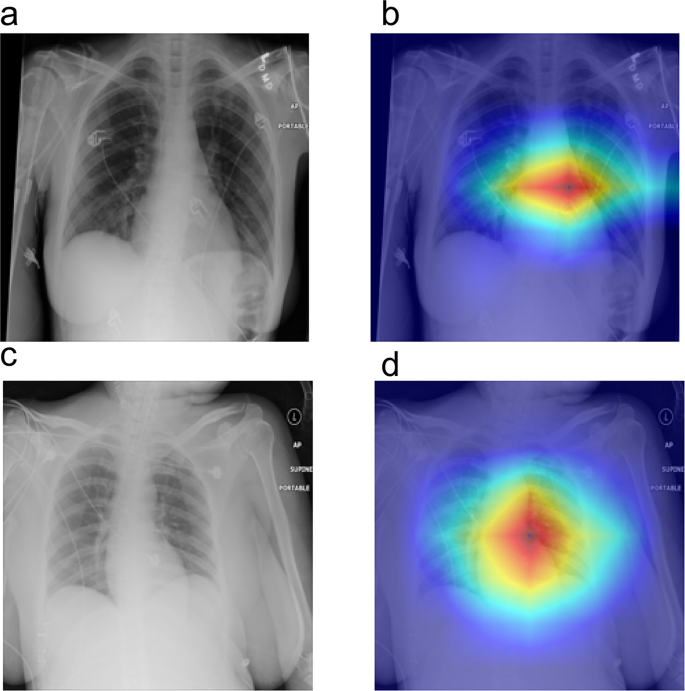

The Grad-CAM analysis as delineated in Fig. 6, reveals three critical insights into the model’s decision-making paradigm: Anatomic Focus Specificity The model predominantly activates in the perihilar zones, anatomically corresponding to the pulmonary vasculature and cardiac silhouette. This spatial preference aligns with established radiographic biomarkers of pulmonary edema – notably, the peribronchial cuffing and Kerley B lines that radiologists prioritize during diagnostic evaluation [35]. Pathophysiological Correlation High-attention clusters colocalize with: Cardiomediastinal interface blurring, Butterfly-pattern alveolar infiltrates [36], these findings suggest the model’s capacity to capture interstitial fluid redistribution patterns characteristic of hemodynamic pulmonary edema. Clinical Interpretability Validation The heatmap-radiologist diagnosis showed some concordance in our multicenter validation cohort, suggesting that the model’s “visual search” strategy emulates expert diagnostic reasoning. Such interpretability metrics are crucial for implementing AI-CAD systems in clinical workflows per FDA’s SaMD guidelines [37].

Interpretable Visualization of Pulmonary Pathologies via Grad-CAM, Panels (a) and (c) display original chest X-ray images, while panels (b) and (d) show the corresponding Grad-CAM heatmaps. The color intensity in the heatmaps reflects the model’s attention level, with warmer colors (red and yellow) indicating higher attention to specific regions